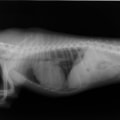

A・B:猫の肥大型心筋症による胸水の貯留 正面像と側面像

C:猫の肥大型心筋症による肺水腫 側面像

D:Cの肺水腫治癒後 側面像